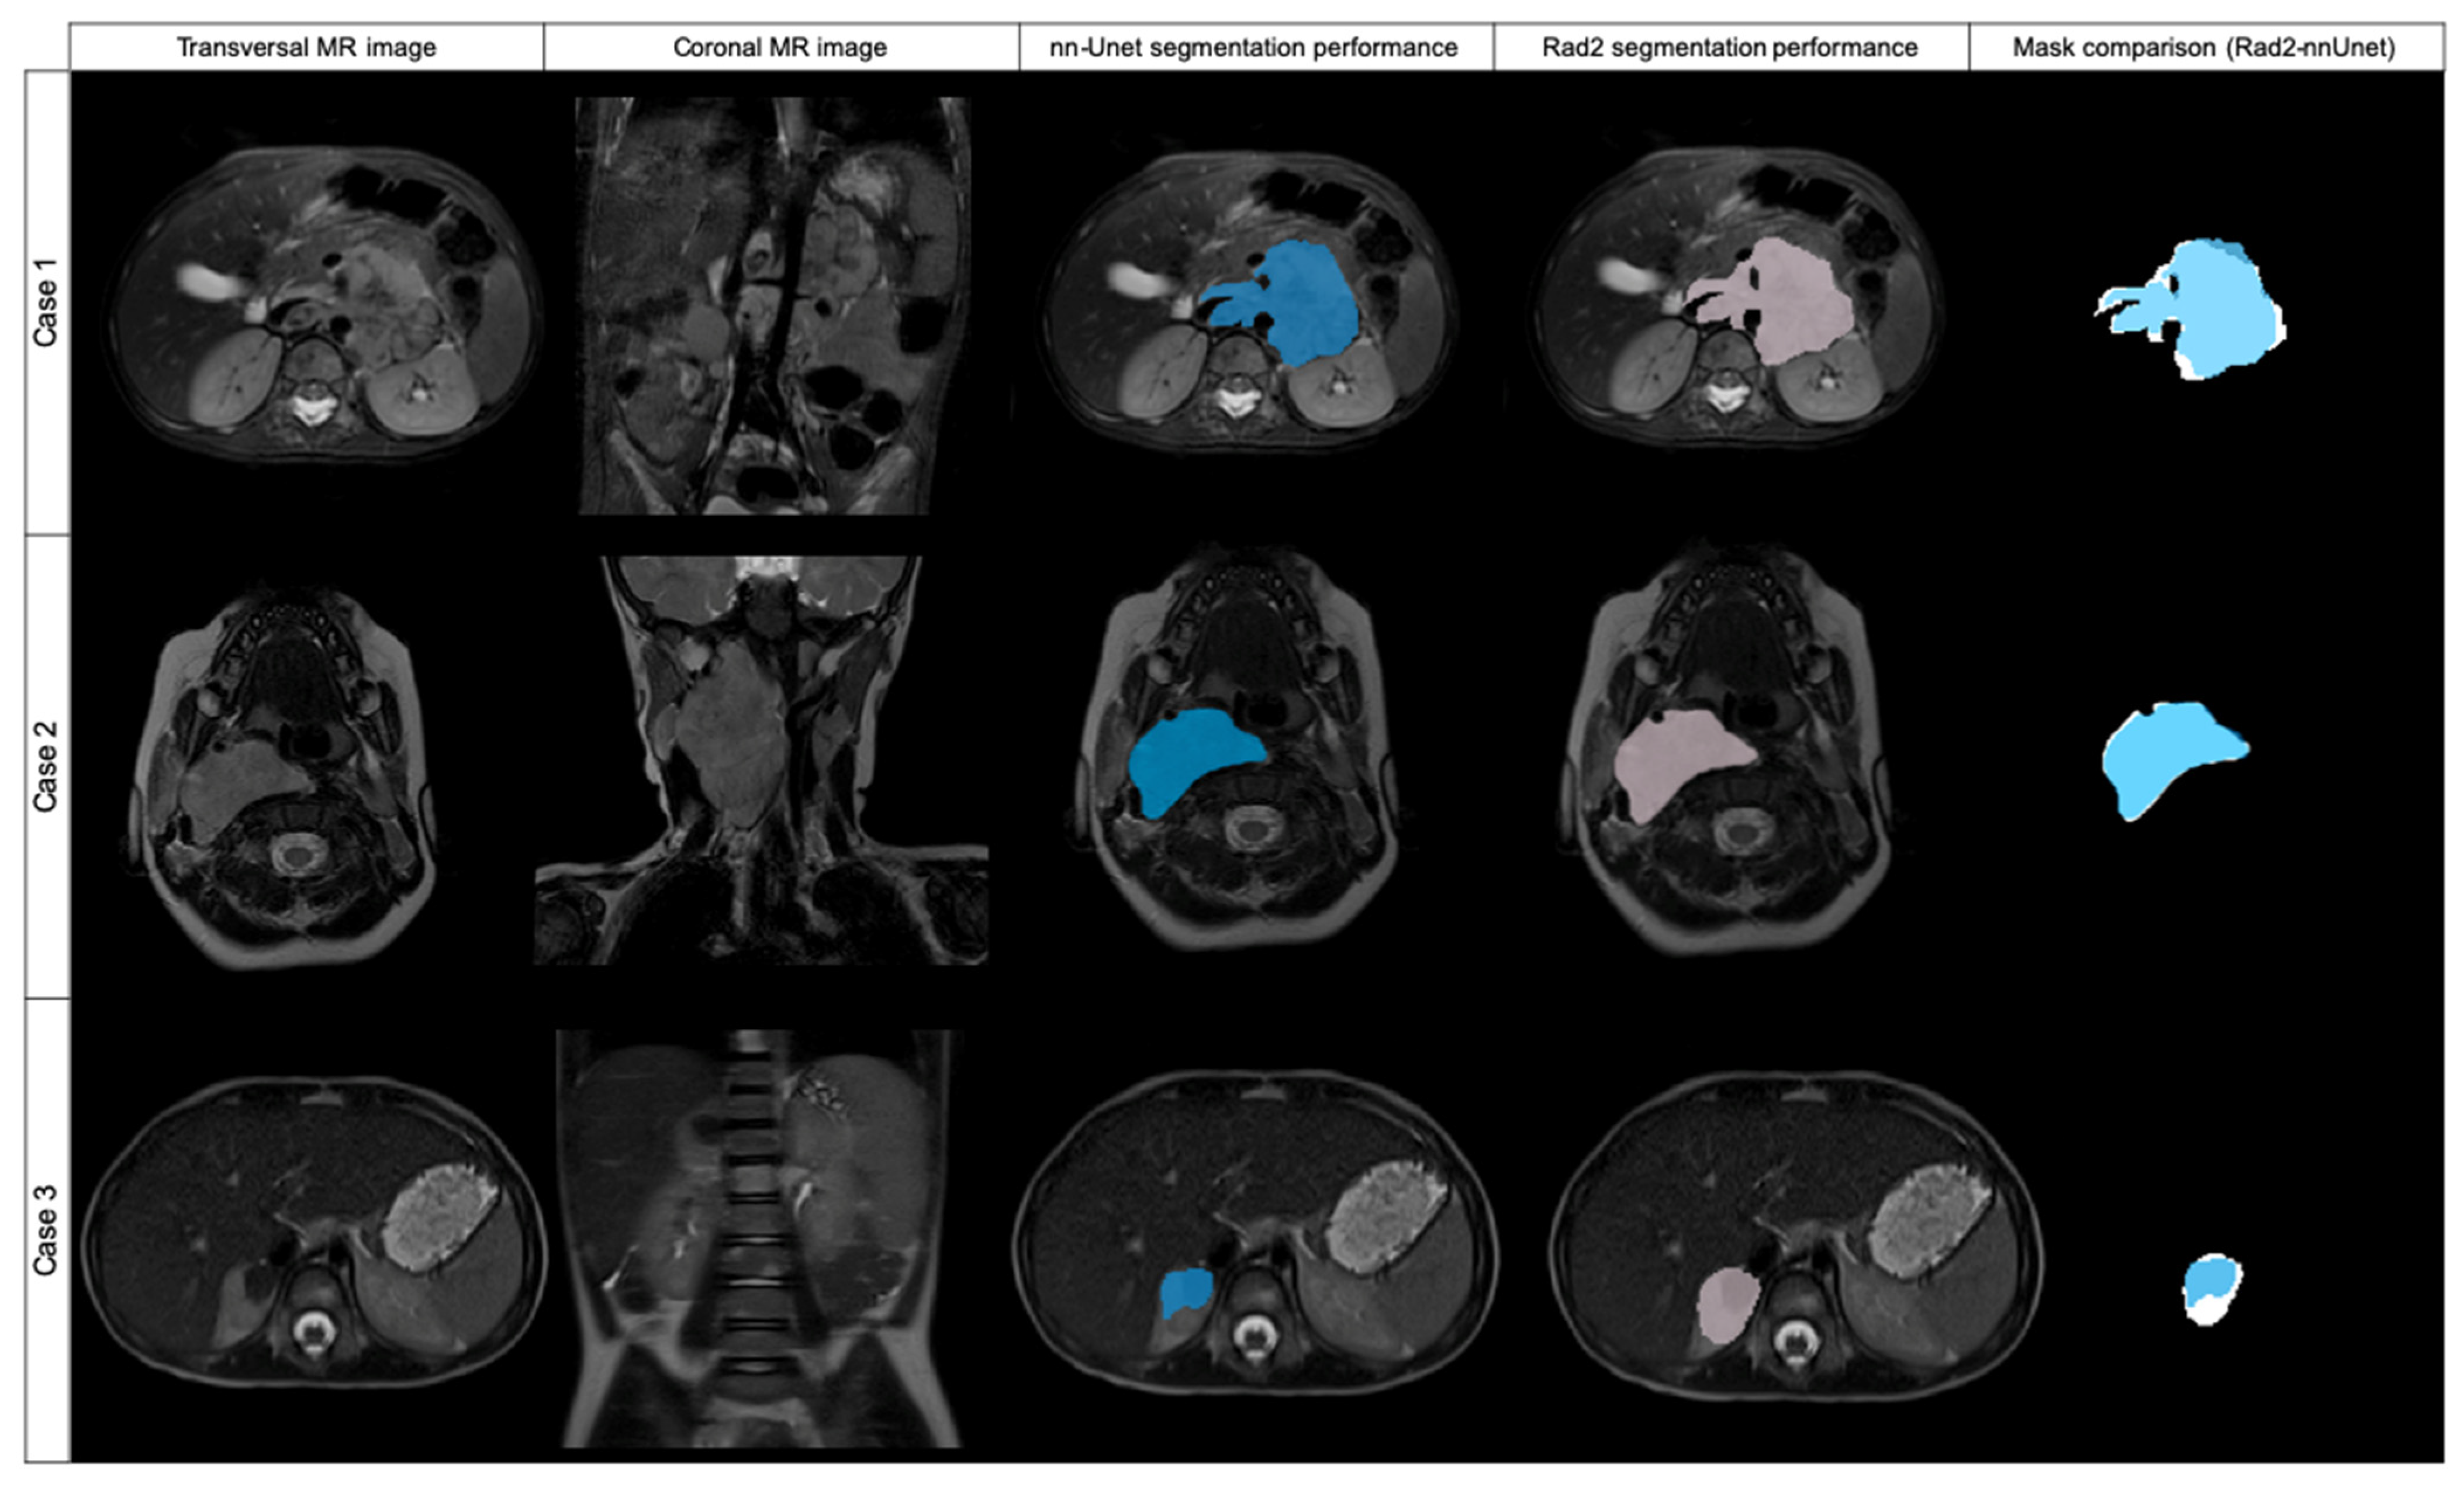

Figure 4. Original transversal and coronal MR images and examples of three cases automatically segmented by nnU-Net (blue labeled) and Radiologist 2 (pink labeled), with mask superposition for comparison. Case 1 was segmented in T2w fat-sat with a DSC of 0.869. Case 2 was segmented on T2w and the DSC obtained was 0.954. Case 3 was segmented with a DSC of 0.617.